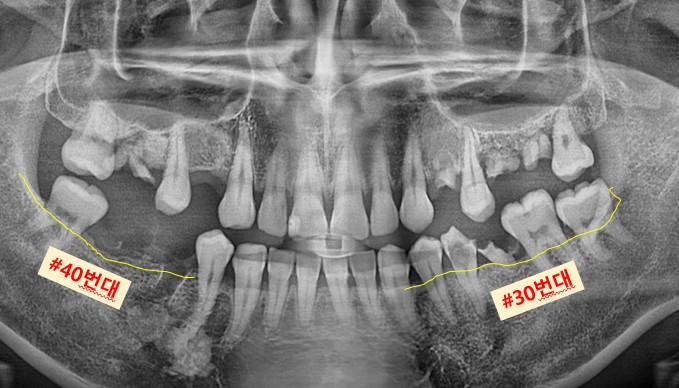

▲ 초진 파노라마 사진

표시된 곳들을 보시면 앞서 말씀드린 것과 같이 잔존 치근들만 남아있는 모습입니다.

노란 선으로 표시된 부분들은 보시면 잇몸뼈가 없어서 내려앉은 모습을 확인할 수 있습니다.

픽스처를 심을 잇몸뼈가 있어야 제대로 심고 잇몸뼈와 잘 결합이 될 수 있기에

#30번대 #40번대 뼈이식부터 먼저 도와드렸습니다.